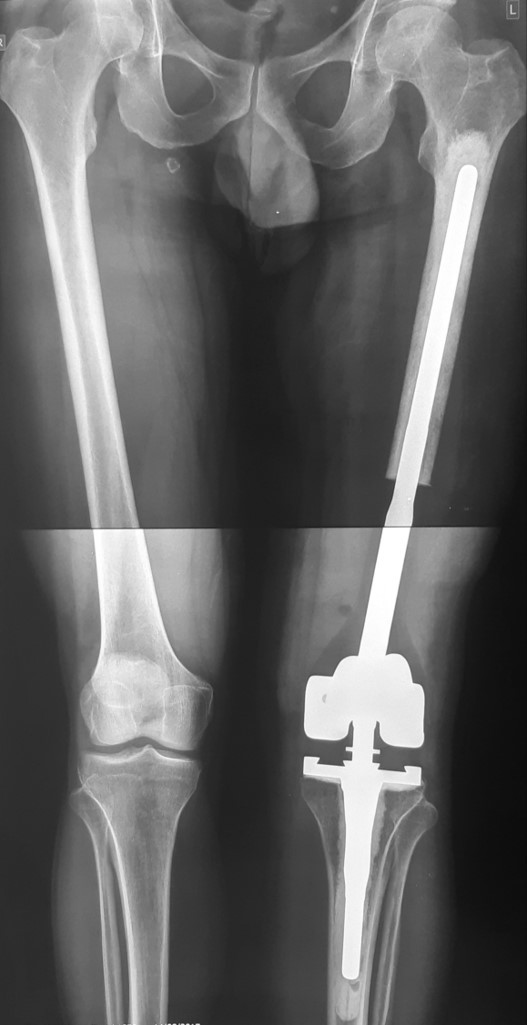

2. Остеосаркома большеберцовой кости

17-летний юноша обратился в МЦ ''Наири'' с жалобами на боли в области коленного сустава. После прохождения обследования у пациента была диагностирована остеосаркома большеберцовой кости.

После получения предоперационной химиотерапии в МЦ ''Наири" была проведена органосохраняющая операции – сегментарная резекция верхней трети большеберцовой кости и коленного сустава, замещение образовавшегося костно-суставного дефекта индивидуальным, изготовленным на заказ эндопротезом. В послеоперационном периоде пациент продолжил показанную по протоколам химиотерапию. В настоящее время лечение завершено, признаков прогрессирования заболевания нет, оперированная конечность функционально пригодная, опороспособность полная.

До операции

После операции